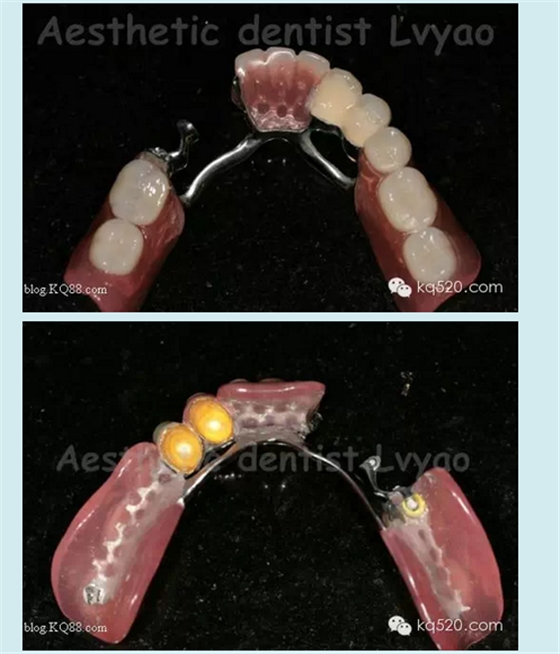

有關(guān)修復(fù)體細節(jié)影像

套筒金沉積外冠效果更佳